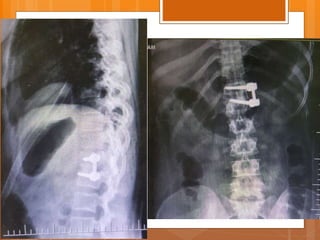

 Female

 21 y/o

 Back pain from 1.5 years ago

 Exacerbated after child delivery (9m ago)

 Pain radiated to right leg from 7m ago

P/E

 ↓L3 , L4 force

 right clonus

 ↓ achilles DTR

 QC DTR normal

 Babinski sign normal

 Intermittent Bladder dysfunction

 Sensory normal

Case presentation  Female 21 y/o  Back pain from 1.5 years ago  Exacerbated after child delivery (9m ago)  Pain radiated to right leg from 7m ago

P/E  ↓L3 ,L4 force  right clonus  ↓ achilles DTR  QC DTR normal  Babinski sign normal  Intermittent Bladder dysfunction  Sensory normal